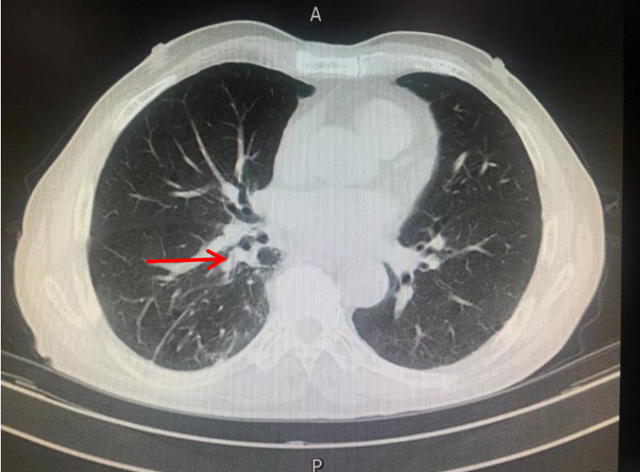

2014年,古稀之年的刘先生,因心累气促,在外院检查发现右肺肿瘤,经手术切除后确诊为肺腺癌早期,术后规律复查。2017年肿瘤复发,并伴有多处淋巴结及肺内转移,诊断为晚期肺癌。

拒绝行放化疗后,刘先生病情进行性加重……外院医生多次沟通后,刘先生又接受了放射治疗,但放疗结束仅5个月肿瘤又长大了。

此时,仍拒绝行全身化疗的刘先生慕名找到西南医科大学附属中医医院肿瘤·血液病科学科主任廖大忠教授,结合患者实际情况及意愿,予以PD-1抑制剂帕博利珠单抗免疫治疗,治疗期间配合中医药增效解毒,患者全程耐受,不良反应逐渐减轻至消失,同时肿瘤缩小。

此后,刘先生一直坚持在肿瘤·血液病科(忠山院区)行免疫联合中医药治疗,从2019年3月至今,已4年时间,刘先生除偶尔咳嗽外,无其他不适。谁能想到这样一个年逾八旬、精神矍铄的老人竟然是位晚期肺癌患者呢?